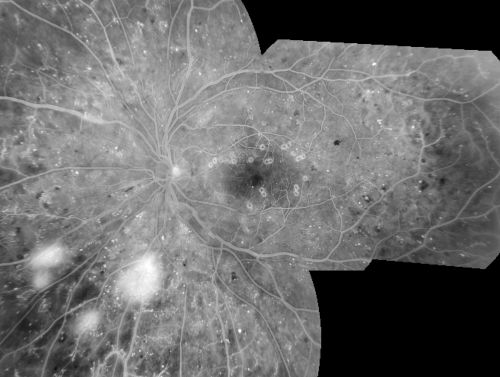

Proliferative Diabetic Retinopathy in patient with Moyamoya Disease

28-year-old womandiabetic since age nine, and she also has had multiple strokes. OD is 20/30, OS is 20/30.